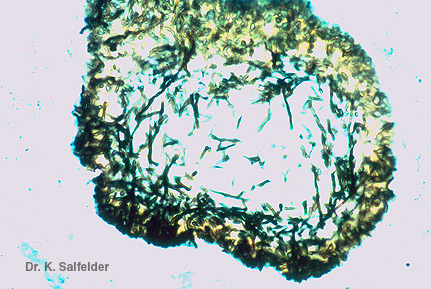

Abb. 16,45: Myzetome

Emmyzetom. Druse mit deutlich erkennbaren Hyphen bei spezieller Pilzfaerbung. Grocottmethode